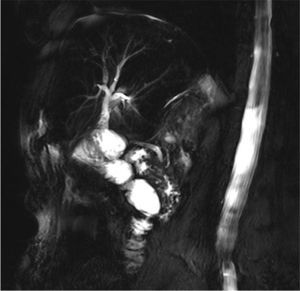

An 84-year-old patient had undergone laparoscopic cholecystectomy for acute cholecystitis. Six months later, she was diagnosed with stenosis of the main bile duct. Endoscopic retrograde cholangiopancreatography could not bridge the stenosis, so percutaneous transhepatic cholangiography was used to pass through to the duodenum with a false passage (Fig. 1). Surgery confirmed the presence of the false passage and extensive stenosis of the proximal third of the bile duct (Figs. 2 and 3). Hepaticojejunostomy was performed. The postoperative course was favorable and the patient was discharged on the 7th day post-op. Cholangio-MRI done one month later confirmed the permeability of the anastomosis (Fig. 4).